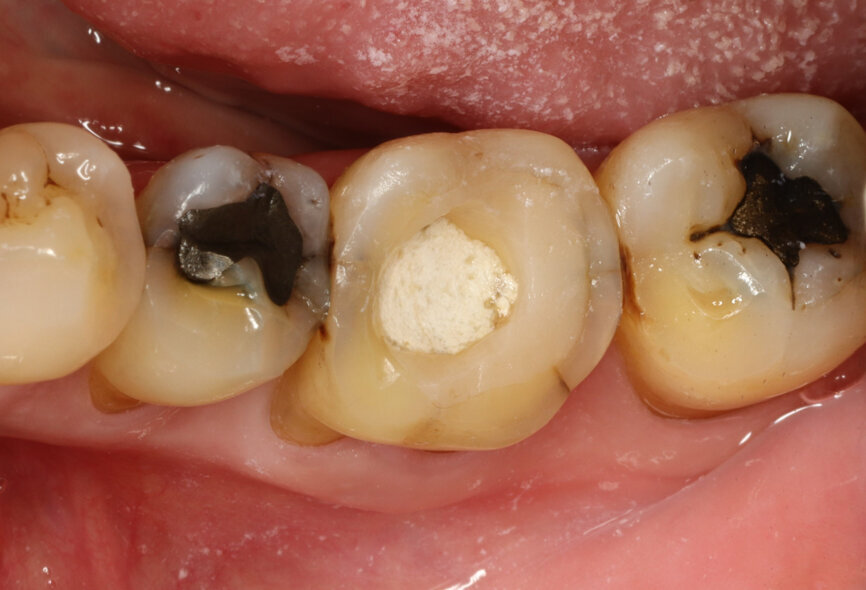

It was possible to verify solid interradicular bone availability (Fig. 5), extending further the limits of the root apices and allowing for a centrally oriented osteotomy. The implant bed preparation started with the use of a needle drill at 800 rpm, followed by the ⌀ 2.2 mm and ⌀ 2.8 mm drills (Figs. 6–10). The implant was placed with the use of ratchet and torque control, reaching the desired final position at a 50 N cm torque value (Figs. 11–13). The socket was then augmented with bovine-derived bone substitute impregnated with advanced platelet-rich fibrin (A-PRF) and finalised with sutures to keep the A-PRF application immobile, and a 3 mm healing abutment was placed (Figs. 14–17).

Fig. 14: Implant in final position with bone augmentation.

Fig. 15: Implant in final position with A-PRF protecting the bone substitute granules.

Fig. 16: Sutures to stabilise the biomaterials in place.